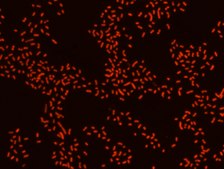

Proteus probe specifically recognizes Proteus species (see images of Proteus vulgaris and Proteus mirabilis). Moreover, it was shown that this probe recognizes Proteus penneri and Proteus hauseri.16

FISH technique was successfully used for clinical detection of Proteus spp. in artificial urine medium and urine samples from patients with UTIs. The probe was able to detect 11 strains of P.mirabilis, 6 strains of P. vulgaris, 2 strains of P.penneri and one strain of P. hauseri.16 The probe can also be used to detect P. mirabilis and P. vulgaris pure culture (as described in the figure legends). FISH can also be implicated to detect Proteus spp. in colon sections embedded in paraffin.17,18 Moreover, FISH can be implicated to identify Proteus spp. in the gut of the medicinal leech.19